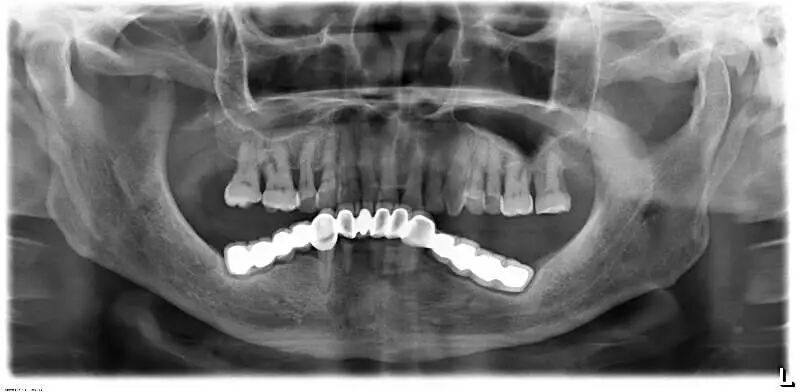

另外,烤瓷桥中的极品——“长江大桥”现象,则是普遍存在于中国各城市各基层牙科的不规范现象,与普通烤瓷桥不同,其本质是一种违反口腔生物力学原理的设计,其最常见的转归是全口牙报废,临床上很多先在基层做,两三年后去医院拆,对口腔健康的影响令人咂舌。

这样的病例实在太多,公立医院和部分高端民营口腔机构每年都要拆除很多例,后续治疗则费时费事费钱费脑筋,而且此类患者来源于社会各阶层,我见过的病例包括一些同事医生(非牙医)的父母,医生的健康意识不代表其家人,而你无法想象其中一例是拥有几百亿资产的企业家,医疗信息不对称应该是主要因素。